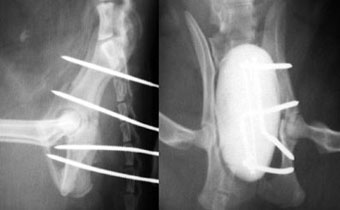

体重3kg、1歳齢の犬。

腸骨骨折と腹壁ヘルニアを起こしていました。

骨折部をプレート法により整復固定した後、腹壁ヘルニアの整復手術を実施しました。

写真上段: 手術前

骨盤の一部が割れて内側に変位しています。

写真下段: 手術後